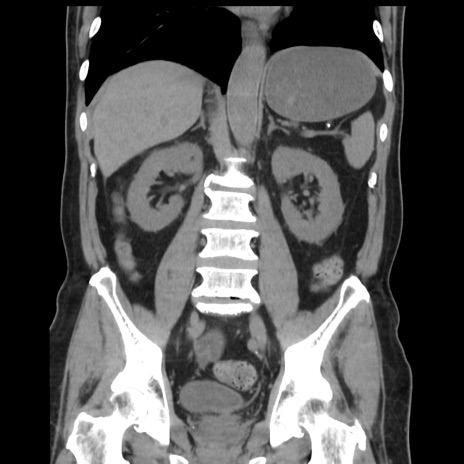

症例16(冠状断像)

【症例】 70歳代男性

【主訴】 腹痛、嘔吐

【現病歴】 約1ヶ月前より間欠的に腹痛と嘔吐あり、当院消化器内科を受診したところCTで多発する肝臓のLDAを指摘され、精査中であった。以降は消化器症状は安定していたが、2日前より嘔気と腹痛があり、同日より排便・排ガスが消失した。改善認めず、 本日、救急外来を受診した。

【既往歴】 大腸ポリープ切除後。

【身体所見】意識清明・会話良好、BT 36.3℃、BP 127/80mmHg、 P 80bpm、腹部:膨満あり、平坦・軟、上腹部正中および下腹部正中に圧痛あり、反跳痛なし、筋性防御なし。

【データ】WBC 7200、CRP 0.77